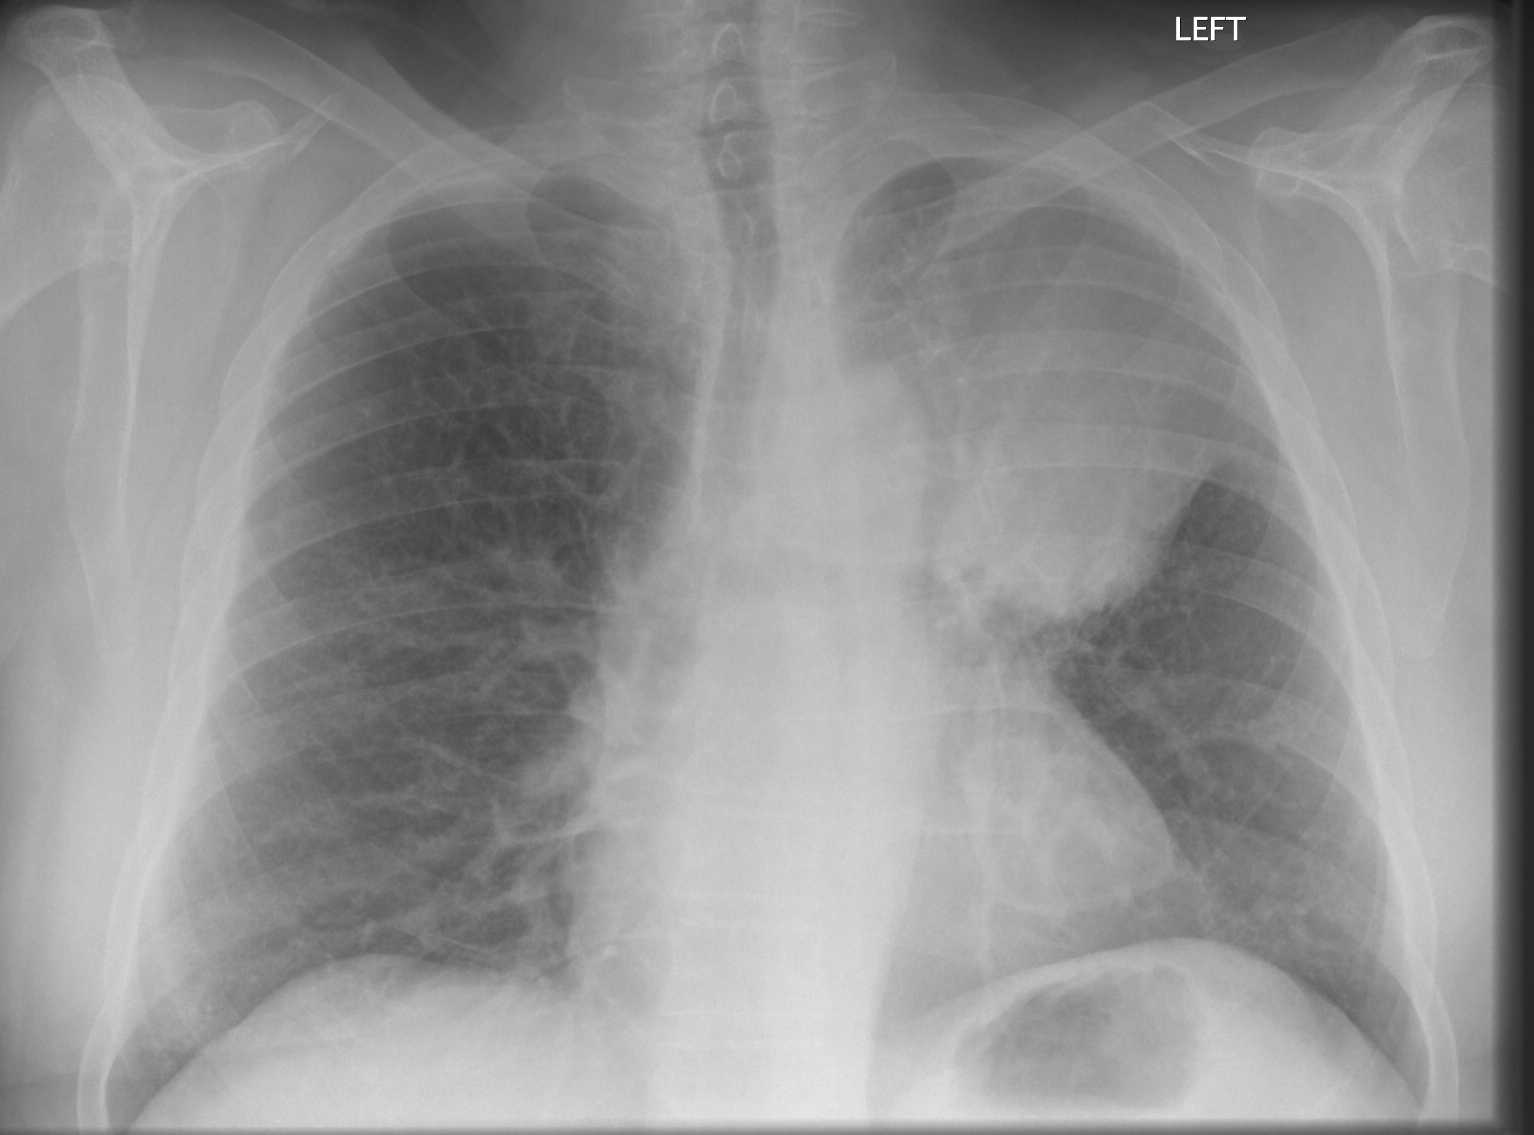

Pneumonia

Feature Description

Consolidation Lobar or segmental increased opacity obscuring lung detail.

Air bronchogram Visible air-filled bronchi within opacified lung parenchyma.

Silhouette sign Loss of normal borders (e.g. heart border, diaphragm) due to adjacent consolidation.

Left middle lobe pneumonia versus normal lung

Comparison of a normal lung and left middle lobe pneumonia